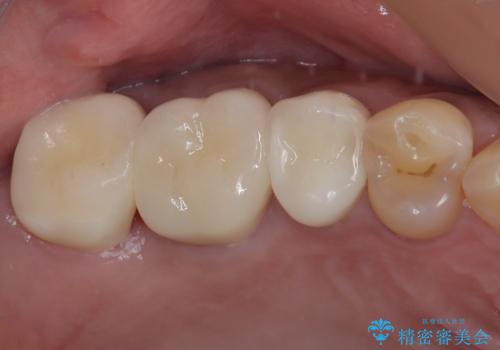

- 前歯の歯並びやむし歯治療の跡、奥歯の銀歯を気にして来院された患者様です。

インビザラインによる矯正治療の後に虫歯や銀歯をセラミックにて補綴することとしました。

前歯のむし歯治療の跡や奥歯の目立つ銀歯がなくなり、明るい口元になりました。